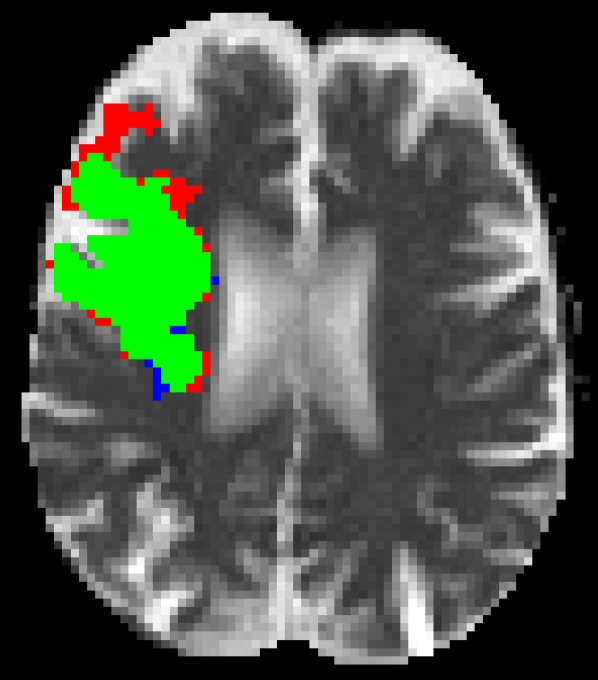

Representative examples of the qualitative results from the proposed method can be found in Figure 4. Cases 9 and 15 represent the overall results of the proposed methodology, correctly detecting the lesions in most cases with an outline that approximates the provided gold standard. Among the observed limitations are inaccurate borders and over/under segmentation of certain regions. For instance, in case 5 the lesion was undersegmented due to a heterogeneous appearance of the gold standard lesion while in case 13 two false positive lesions are detected due to the previous existence of chronic stroke lesions with a similar appearance.

Figure 4: Output segmentation masks of representative cases from the training images of ISLES 2015 SISS dataset. On all images, true positives are denoted in green, false positives in red and false negatives in blue.